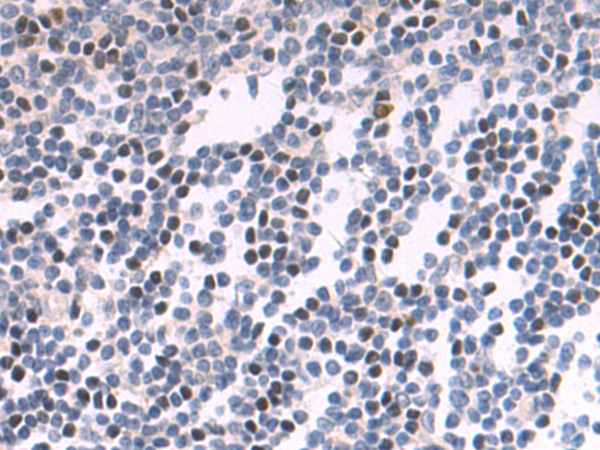

分类: 科研抗体货号: P04297别名: CSDD1; LIN28; LIN-28; ZCCHC1; lin-28A应用: IHC反应种属: Human, Mouse